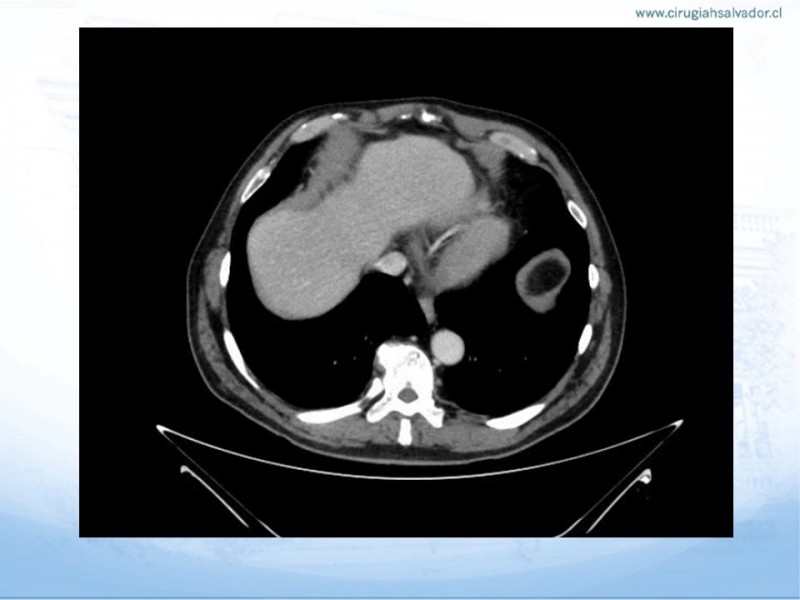

Hitos Anatomo-Quirúrgicos en Gastrectomía

Especialidad: Digestivo Alto | Autor: Dr. Felipe Farfán Flores Residente Cirugía